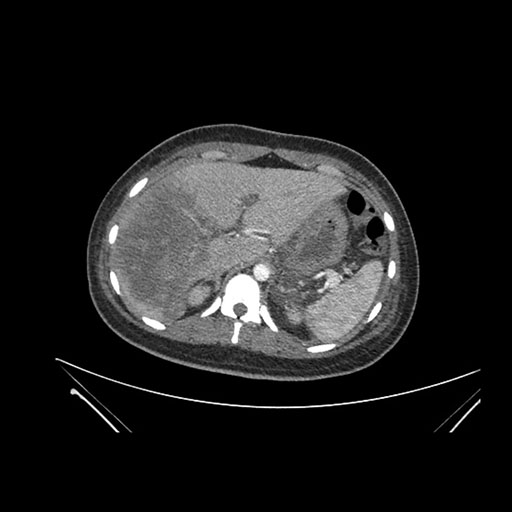

Axial Arterial

Imaging analysis

Based on initial findings, which issue(s) would you be most concerned about?